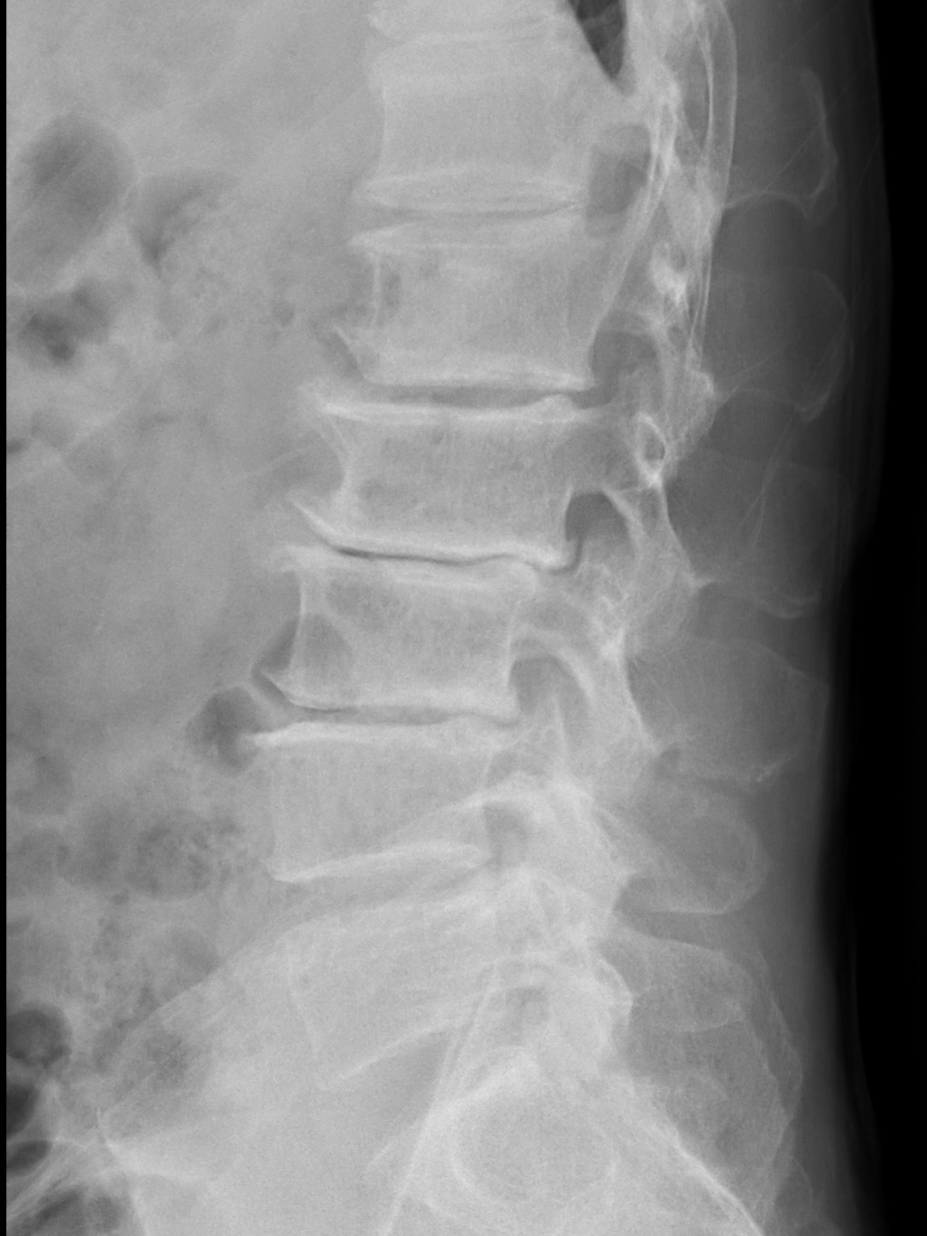

然而患者需行多节段腰椎融合

如何规避神经损伤风险?

术前打印解剖模型

提前规划手术方案

陈勇主任在医学3D打印技术团队的支持下,通过术前采集患者目标椎体的三维信息,运用3D打印技术重建脊柱三维模型,设计椎弓根螺钉的置入钉道,有效控制置钉的位置、方向及角度,从而提高置钉的准确性和成功率,以减少术中置钉过程中神经损伤的风险。

▲3D打印直观显示椎体结构,指导手术精准置钉